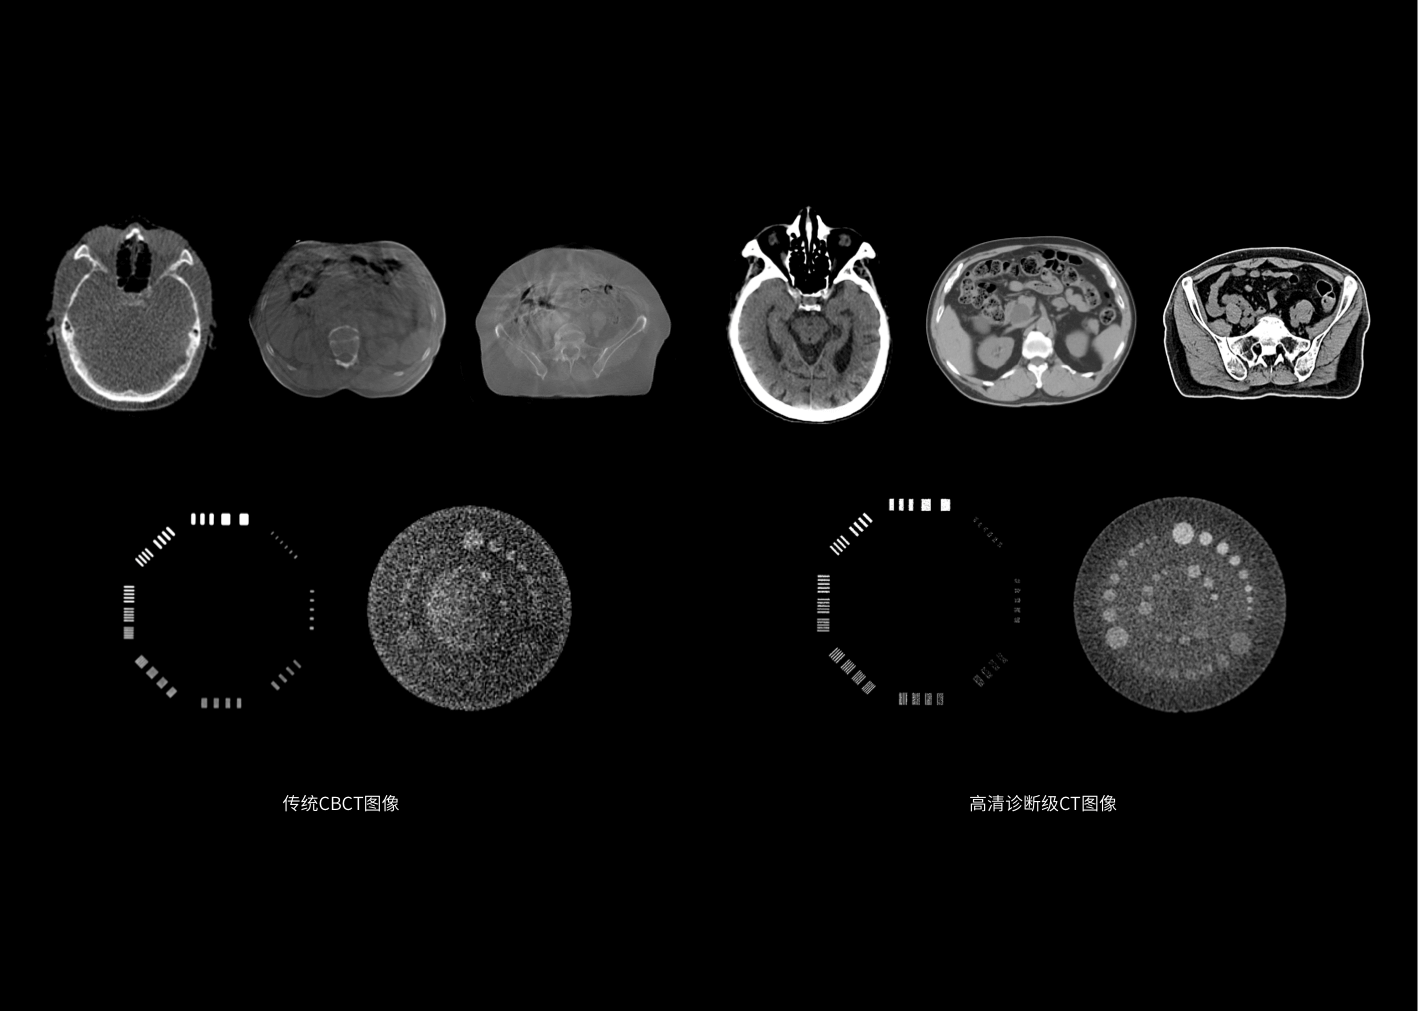

开创诊断级螺旋CT与直线加速器一体化跨界融合,依托高清诊断级图像引导,革新智能临床工作流程,达到精准放疗新高度,拓展放疗新应用,开启个体化精准放疗2.0时代。

50cm FOV, 100cm扫描长度,满足多种场景下的CT影像大成像范围要求。

诊断级CT精确的电子密度信息提供精准剂量计算的金标准。

诊断级高清CT助力监测肿瘤变化,及时调整治疗方案,护航各分次放疗精确实施。